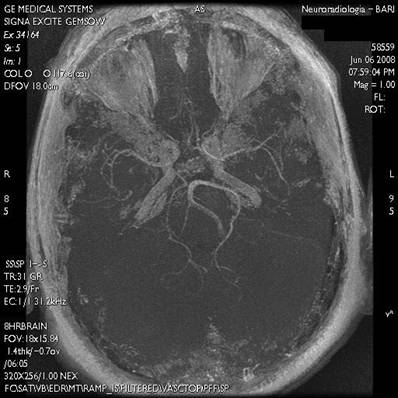

The intraoral examination revealed destructive decay of tooth number 12 and necrotic residues of teeth 15 and 27 (Fig. 1).

Fig 1

RX-OPT of the patient